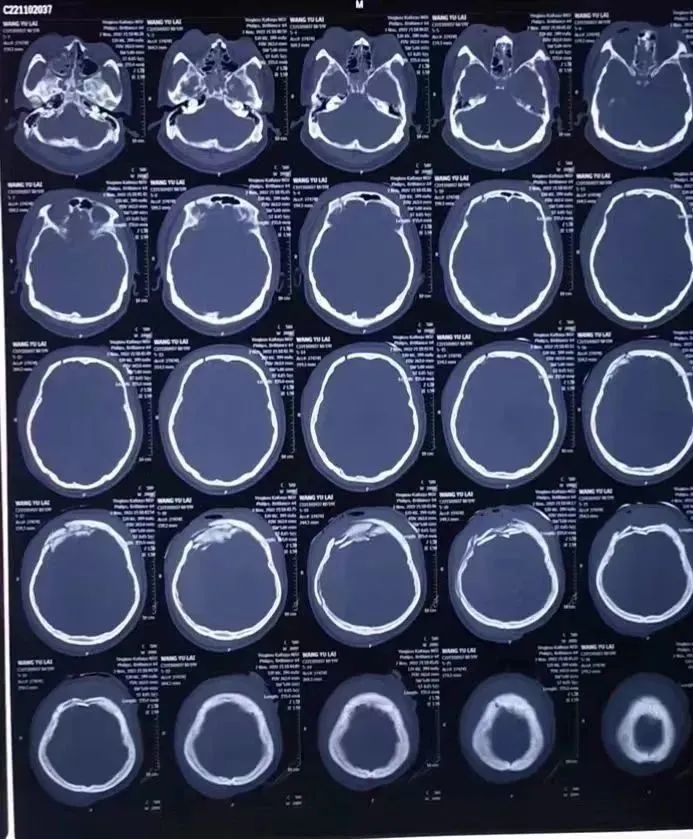

(术后影像报告)

手术过程一切顺利,止住了静脉窦的出血,清除了脑内血肿。术后十天患者意识逐渐恢复,一个月后康复出院。三个月后顺利完成颅骨修补。

(颅骨修补术前后对比图)